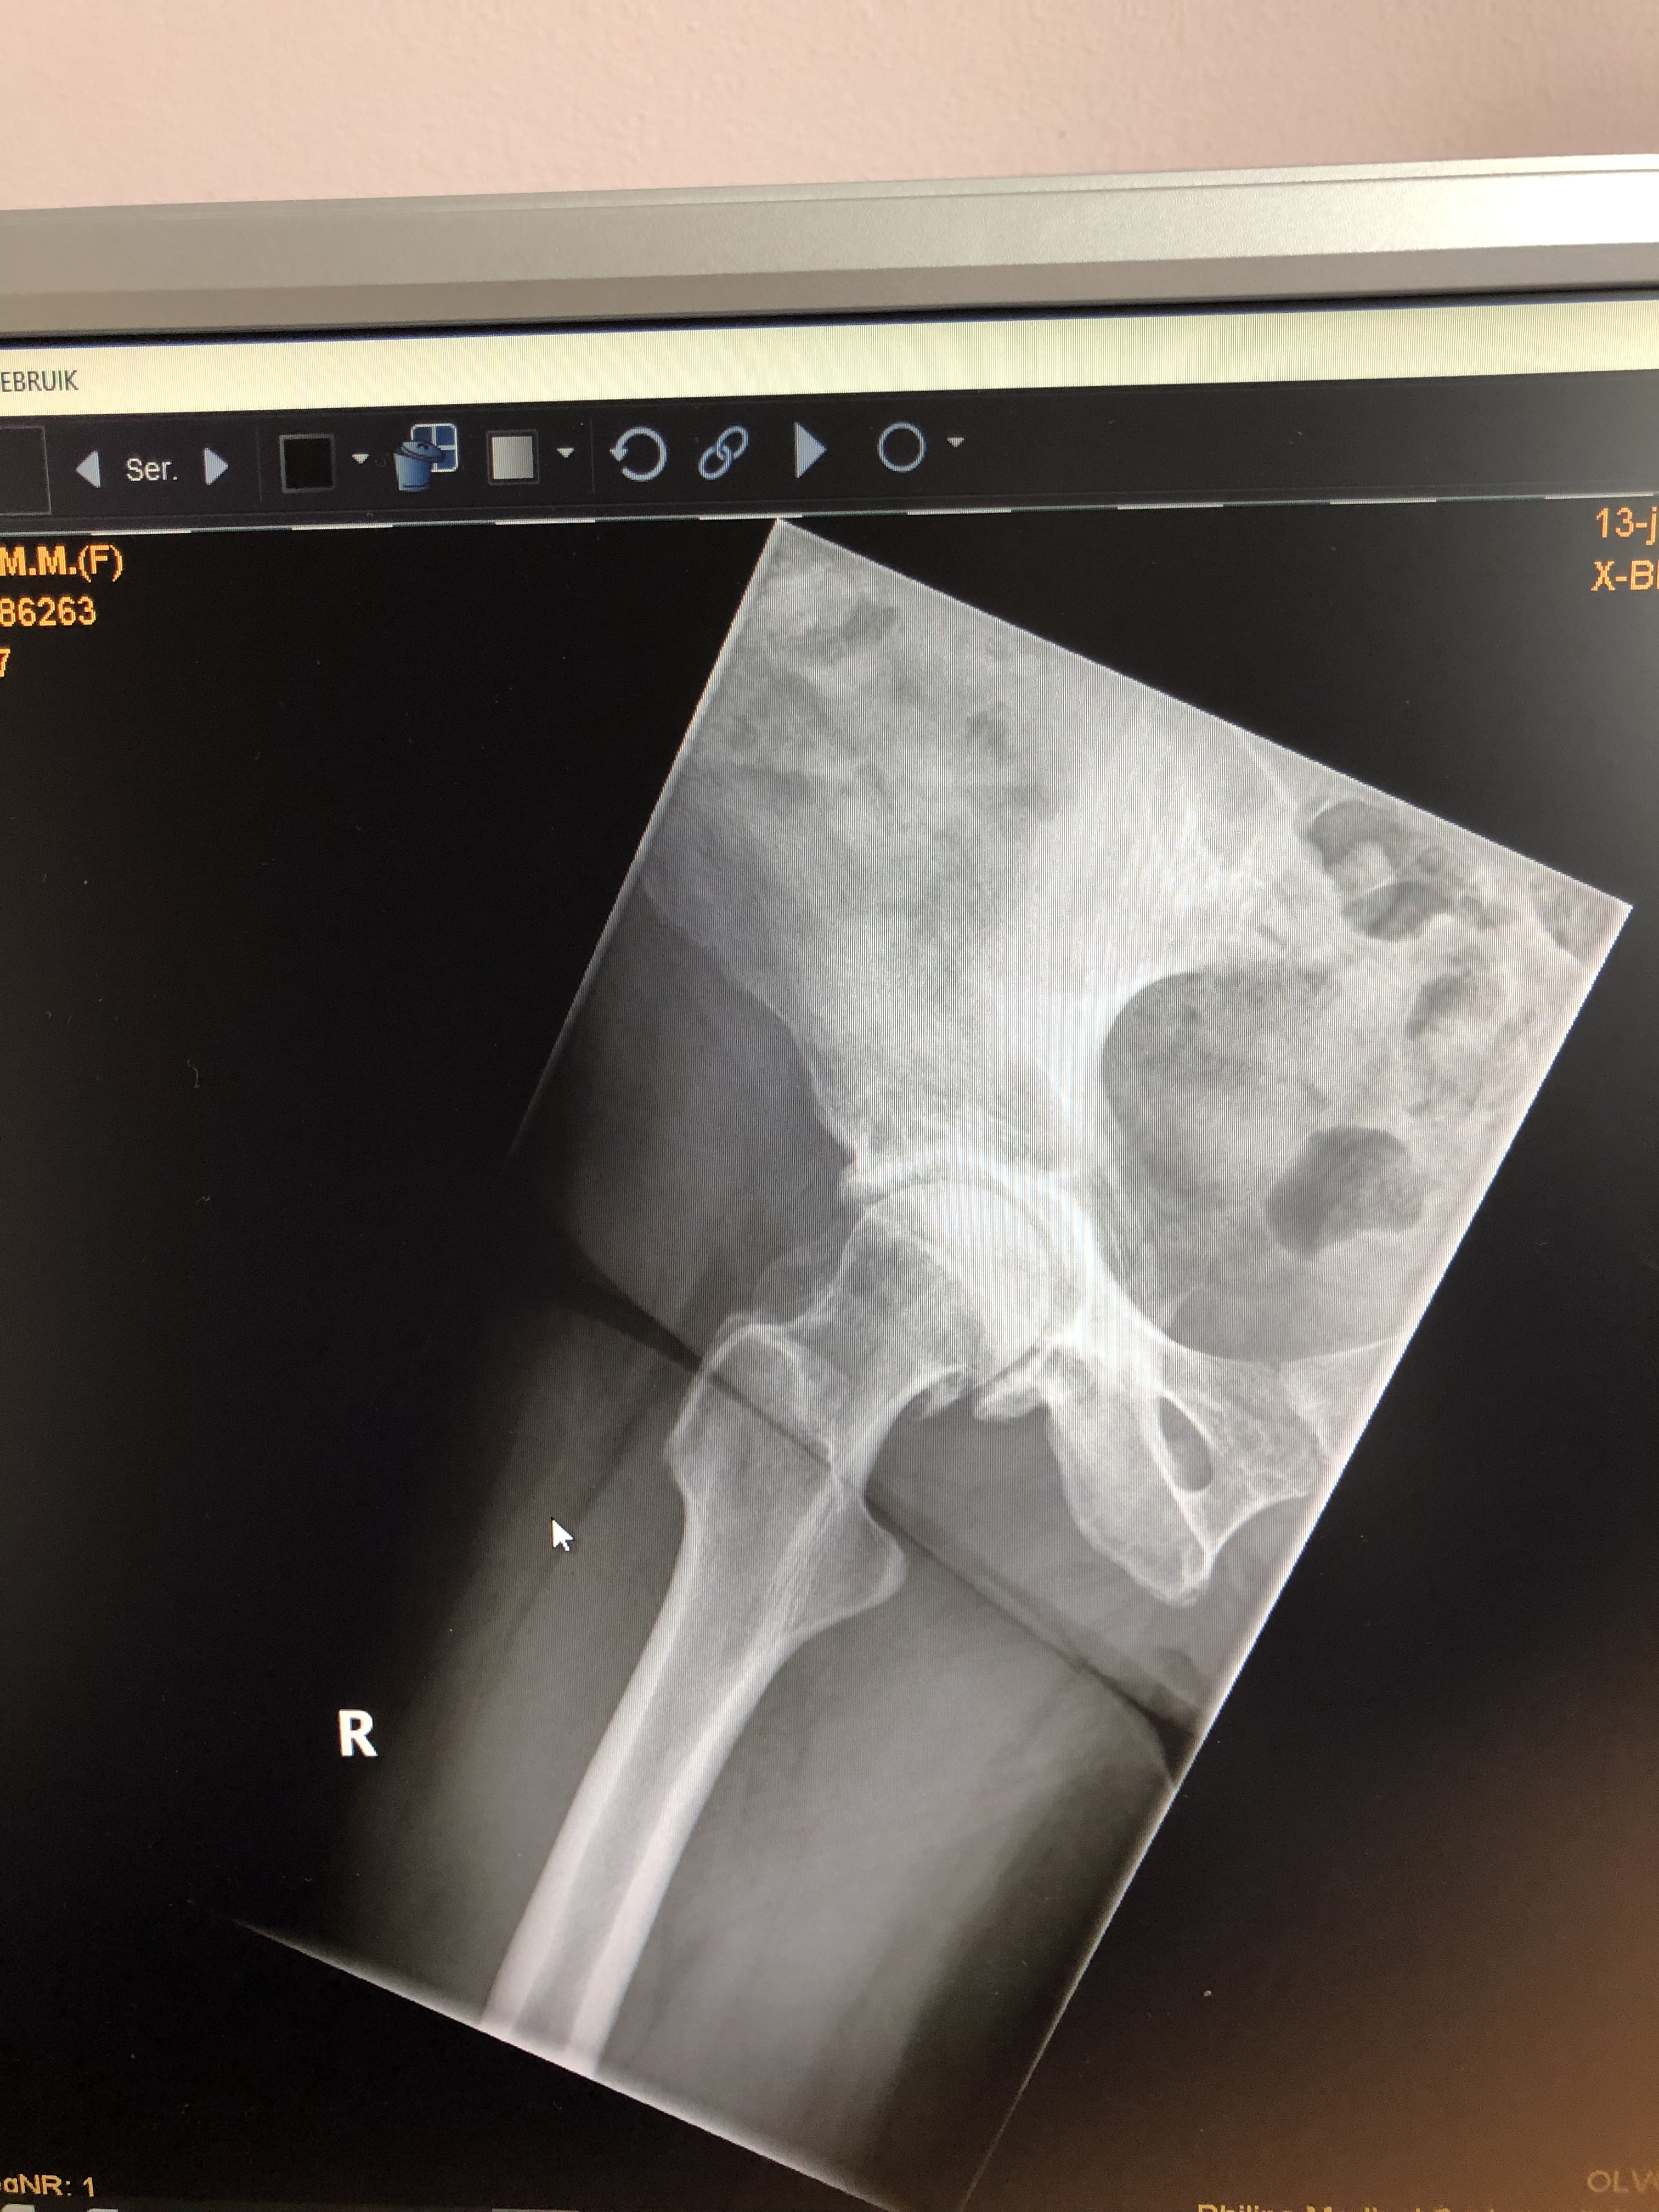

Nou dat is hem dan. Mijn rechter heup. Doorgelicht. Typisch gevalletje van versleten heup. Rond de kop van de heup, waar kraakbeen hoort te zitten om stoten en bewegingen op te vangen zit niets meer. En dat betekent dat je, in mijn geval, niet meer lang kunt staan en lopen. De pijn viel bij mij mee, daarom heb ik ook zo lang gewacht. Er zijn allerlei filmpjes op internet waar je kunt bekijken wat ze precies doen, tijdens zo’n operatie. Wilde ik niet zien. Wat heb je er aan? Maakt alleen maar angstig. En het is toch al geen feest…